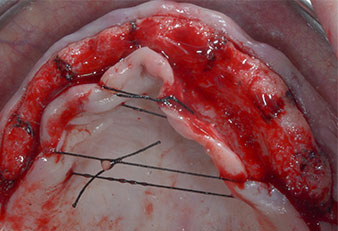

Pose d'implants

Fig. 2 : Une fois l'incision pratiquée à mi-hauteur de crête et le lambeau muco-périosté préparé, les positions implantaires sont transférées sur l’os.